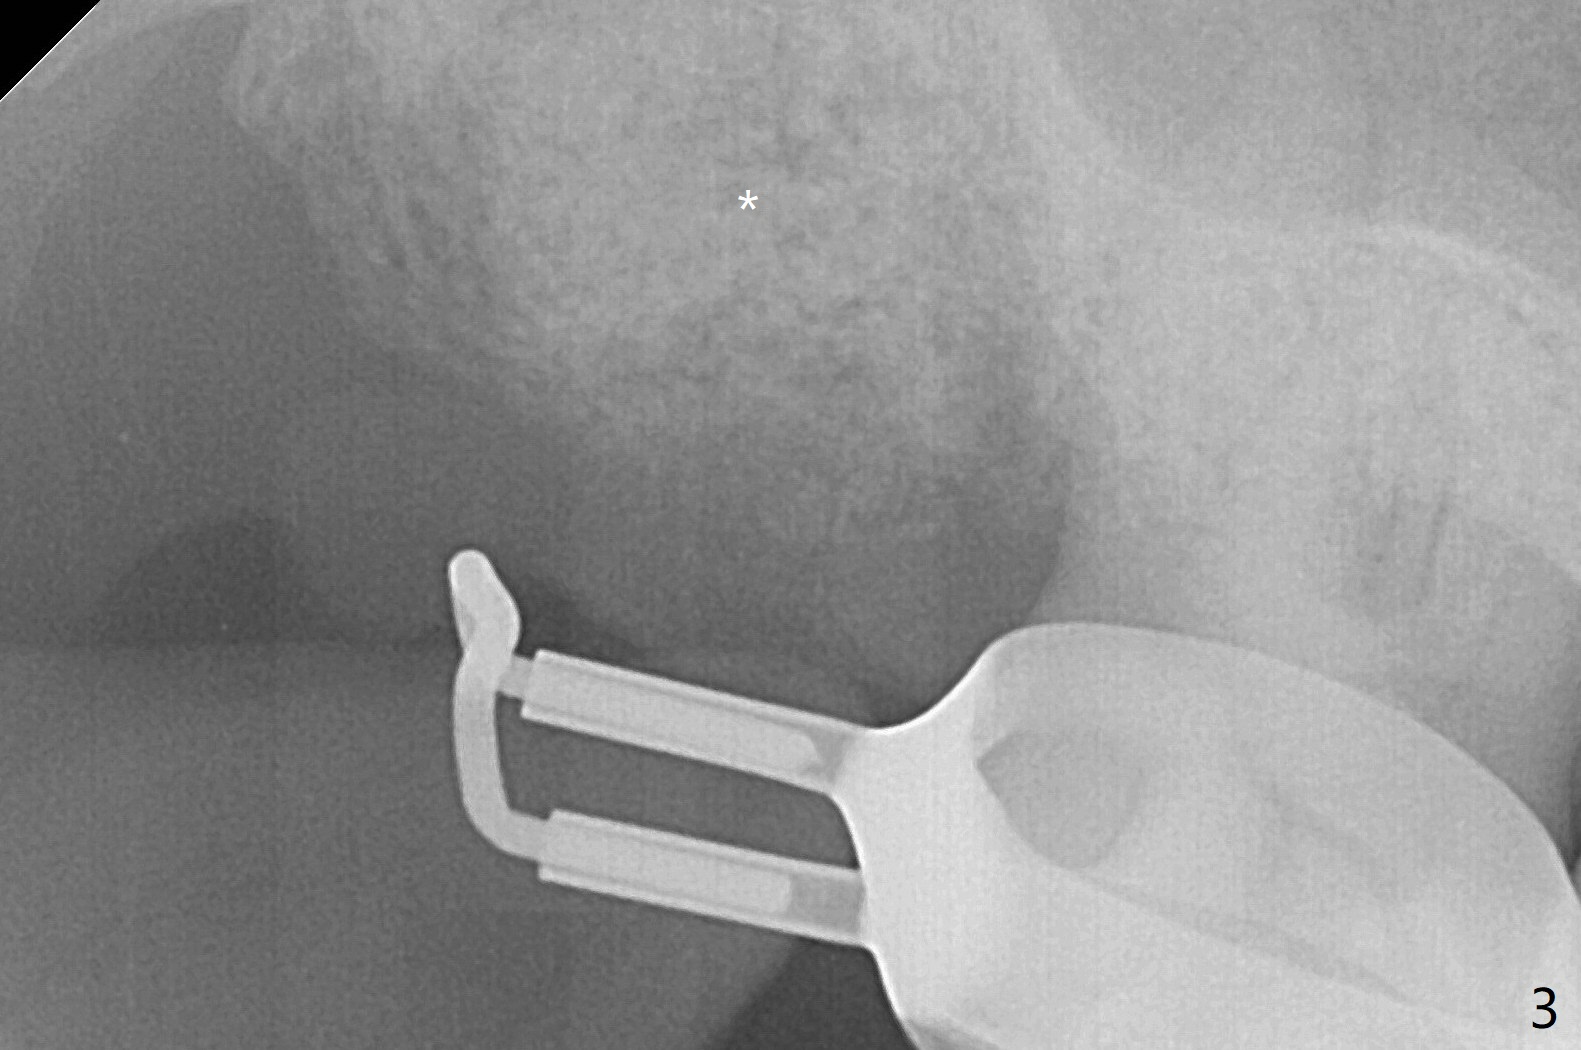

M

A 55-year-old woman requests extraction of the tooth #2 with pain and mobility a few weeks post SRP (Fig.1) and finally agrees with socket preservation (Fig.2,3 *). In fact the mesiobuccal root appears to have been fractured. She is a heavy bruxer (nuts). There is a large amount of granulation tissue in a large single socket. After suture fixation over Osteogen plug and allograft (*), a prefabricated band (B) and loop (L) are cemented in place. Periodontal dressing is applied mainly underneath the loop for wound protection and bone graft and membrane fixation. The central portion of the periodontal dressing remains in place over the socket opening 1 week postop (Fig.4). The removable distal portion of the loop dislodged 23 days postop. The free end of the fixed mesial portion of the loop is irritating; the patient returns the following day. After removal of the spacer, the socket appears to have healed (Fig.5). No bone graft has been lost (Fig.6 *, as compared to immediately postop (Fig.2,3)). Return to Upper Molar Immediate Implant, Trajectory Xin Wei, DDS, PhD, MS 1st edition 04/13/2019, last revision 01/06/2020